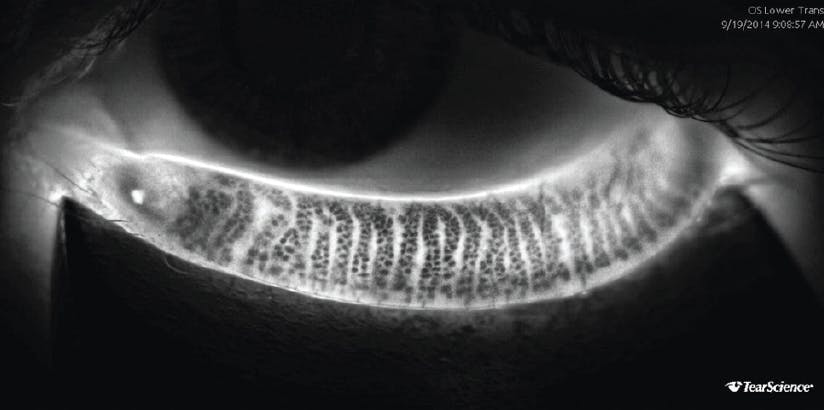

LipiScan noninvasively assesses meibomian gland structure; it uses dynamic illumination to minimize reflections and adaptive transillumination to provide equal lighting across the surface of the eyelids. Normal acini appear as discrete linear groups of light gray circular structures, whereas meibomian gland atrophy is seen as a darker gray absence of those structures. Serial images can be used to track the progress of therapy and improve patient compliance. Once meibomian glands atrophy, their function decreases, and their ability to regenerate is lost. Widespread destruction of glands seen on LipiScan images could therefore identify patients who may be less responsive to LipiFlow treatment (Figures 1–4).14

Figure 1. Dynamic illumination with the LipiScan shows normal meibomian gland acini without dropout.